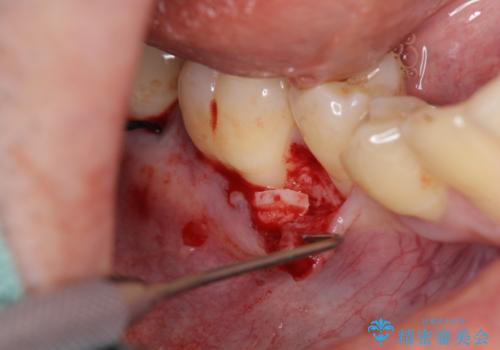

- 定期的にクリーニングに通われている中、右下の歯がどんどん染みるようになってきていることの改善を希望されました。

元々歯ブラシの圧が強く、歯が削れてしまい歯ぐきも下がってしまっている状態です。

数ヶ月知覚過敏薬を塗布し続けましたが改善見られず、下がってしまった歯ぐきを移植により改善する治療計画をたてます。